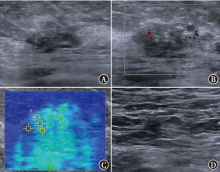

目的探讨常规超声联合剪切波弹性成像(SWE)鉴别诊断非肿块型导管原位癌(DCIS)和浸润性乳腺癌(IBC)的价值。方法选取2019年3月至2022年4月在南京大学医学院附属鼓楼医院收治的102例非肿块型乳腺癌患者作为研究对象,其中DCIS 32例、IBC 70例。比较非肿块型DCIS、IBC患者常规超声参数回声、微钙化、方位、后方回声、血流、腋窝淋巴结、乳腺影像报告与数据系统(BI-RADS)评分及SWE相关参数剪切波速度最大值(SWVmax)、剪切波速度最小值(SWVmin)、剪切波速度平均值(SWVmean)和剪切波速度中位数(SWVmedian),采用二元logistic回归分析鉴别诊断非肿块型DCIS和IBC的独立影响因素。根据多因素分析结果构建列线图预测模型,采用受试者操作特征(ROC)曲线评估预测模型的预测效能,采用校准曲线及决策曲线分析(DCA)评估模型的准确性和实用性。结果非肿块型DCIS、IBC患者间血流(χ2=8.47,P=0.004)、腋窝淋巴结(χ2=9.11,P=0.003)、SWVmaxZ=-3.32,P<0.001)、SWVmeant=3.00,P=0.003)、SWVmedianZ=-2.69,P=0.007)差异均有统计学意义。多因素分析显示,血流(OR=3.56,95%CI为1.28~9.89,P=0.015)、腋窝淋巴结(OR=3.04,95%CI为1.10~8.42,P=0.032)和SWVmaxOR=1.40,95%CI为1.13~1.73,P=0.002)均为鉴别诊断非肿块型DCIS和IBC的独立影响因素。基于血流、腋窝淋巴结、SWVmax构建列线图预测模型。ROC曲线分析显示,血流、腋窝淋巴结、SWVmax、预测模型鉴别诊断非肿块型DCIS和IBC的曲线下面积分别为0.64(95%CI为0.52~0.76)、0.66(95%CI为0.55~0.77)、0.71(95%CI为0.60~0.81)、0.79(95%CI为0.70~0.88),预测模型的鉴别诊断价值高于血流(Z=2.92,P=0.004)、腋窝淋巴结(Z=2.94,P=0.003)、SWVmaxZ=1.88,P=0.060)单独诊断。预测模型鉴别诊断非肿块型DCIS和IBC的C-index为0.77,校准曲线显示模型的预测概率接近实际概率。DCA表明,该模型能提供较高的临床净获益,具有一定的临床实用性。结论常规超声参数中的血流、腋窝淋巴结和SWE相关参数的SWVmax均为鉴别诊断非肿块型DCIS和IBC的独立影响因素,以此构建的列线图预测模型对非肿块型DCIS和IBC具有较高的鉴别诊断价值。

ObjectiveTo investigate the value of conventional ultrasound combined with shear wave elastography (SWE) in the differential diagnosis of non-mass ductal carcinomain situ(DCIS) and invasive breast cancer (IBC).MethodsA total of 102 patients with non-mass breast cancer admitted to Nanjing Drum Tower Hospital, Affiliated Hospital of Nanjing University Medical School from March 2019 to April 2022 were selected as the study objects, including 32 cases of DCIS and 70 cases of IBC. Conventional ultrasound parameters echo, microcalcification, location, posterior echo, blood flow, axillary lymph node, breast imaging reporting and data system (BI-RADS) score and SWE-related parameters maximum shear wave velocity (SWVmax), minimum shear wave velocity (SWVmin), mean shear wave velocity (SWVmean) and median shear wave velocity (SWVmedian) were compared between patients with non-mass DCIS and IBC. Binary logistic regression was used to analyze the independent factors for the differential diagnosis of non-mass DCIS and IBC. Based on the results of multivariate analysis, a nomogram prediction model was constructed and the predictive efficacy of the prediction model was evaluated by receiver operator characteristic (ROC) curve. Calibration curve and decision curve analysis (DCA) were used to evaluate the accuracy and practicability of the model.ResultsThere were statistically significant differences in blood flow (χ2=8.47,P=0.004), axillary lymph nodes (χ2=9.11,P=0.003), SWVmaxZ=-3.32,P<0.001), SWVmeant=3.00,P=0.003), SWVmedianZ=-2.69,P=0.007) between patients with non-mass DCIS and IBC. Multivariate analysis showed that, blood flow (OR=3.56, 95%CI: 1.28-9.89,P=0.015), axillary lymph nodes (OR=3.04, 95%CI: 1.10-8.42,P=0.032) and SWVmaxOR=1.40, 95%CI: 1.13-1.73,P=0.002) were independent factors for distinguishing non-mass DCIS from IBC. A nomogram prediction model was constructed based on blood flow, axillary lymph nodes and SWVmax. ROC curve analysis showed that, the area under the curve of blood flow, axillary lymph nodes, SWVmax, and prediction model for differential diagnosis of non-mass DCIS and IBC were 0.64 (95%CI: 0.52-0.76), 0.66 (95%CI: 0.55-0.77), 0.71 (95%CI: 0.60-0.81), and 0.79 (95%CI: 0.70-0.88), respectively, and the differential diagnostic value of prediction model was higher than that of blood flow (Z=2.92,P=0.004), axillary lymph nodes (Z=2.94,P=0.003), and SWVmaxZ=1.88,P=0.060) alone. The C-index of the prediction model for the differential diagnosis of non-mass DCIS and IBC was 0.77, and the calibration curve showed that the prediction probability of the prediction model was close to the actual probability. DCA showed that this prediction model could provide higher clinical net benefit and had certain clinical practicability.ConclusionBlood flow and axillary lymph nodes in conventional ultrasound parameters and SWVmaxof SWE-related parameters are independent factors in the differential diagnosis of non-mass DCIS and IBC. The nomogram prediction model constructed by this method has a high value in the differential diagnosis of non-mass DCIS and IBC.